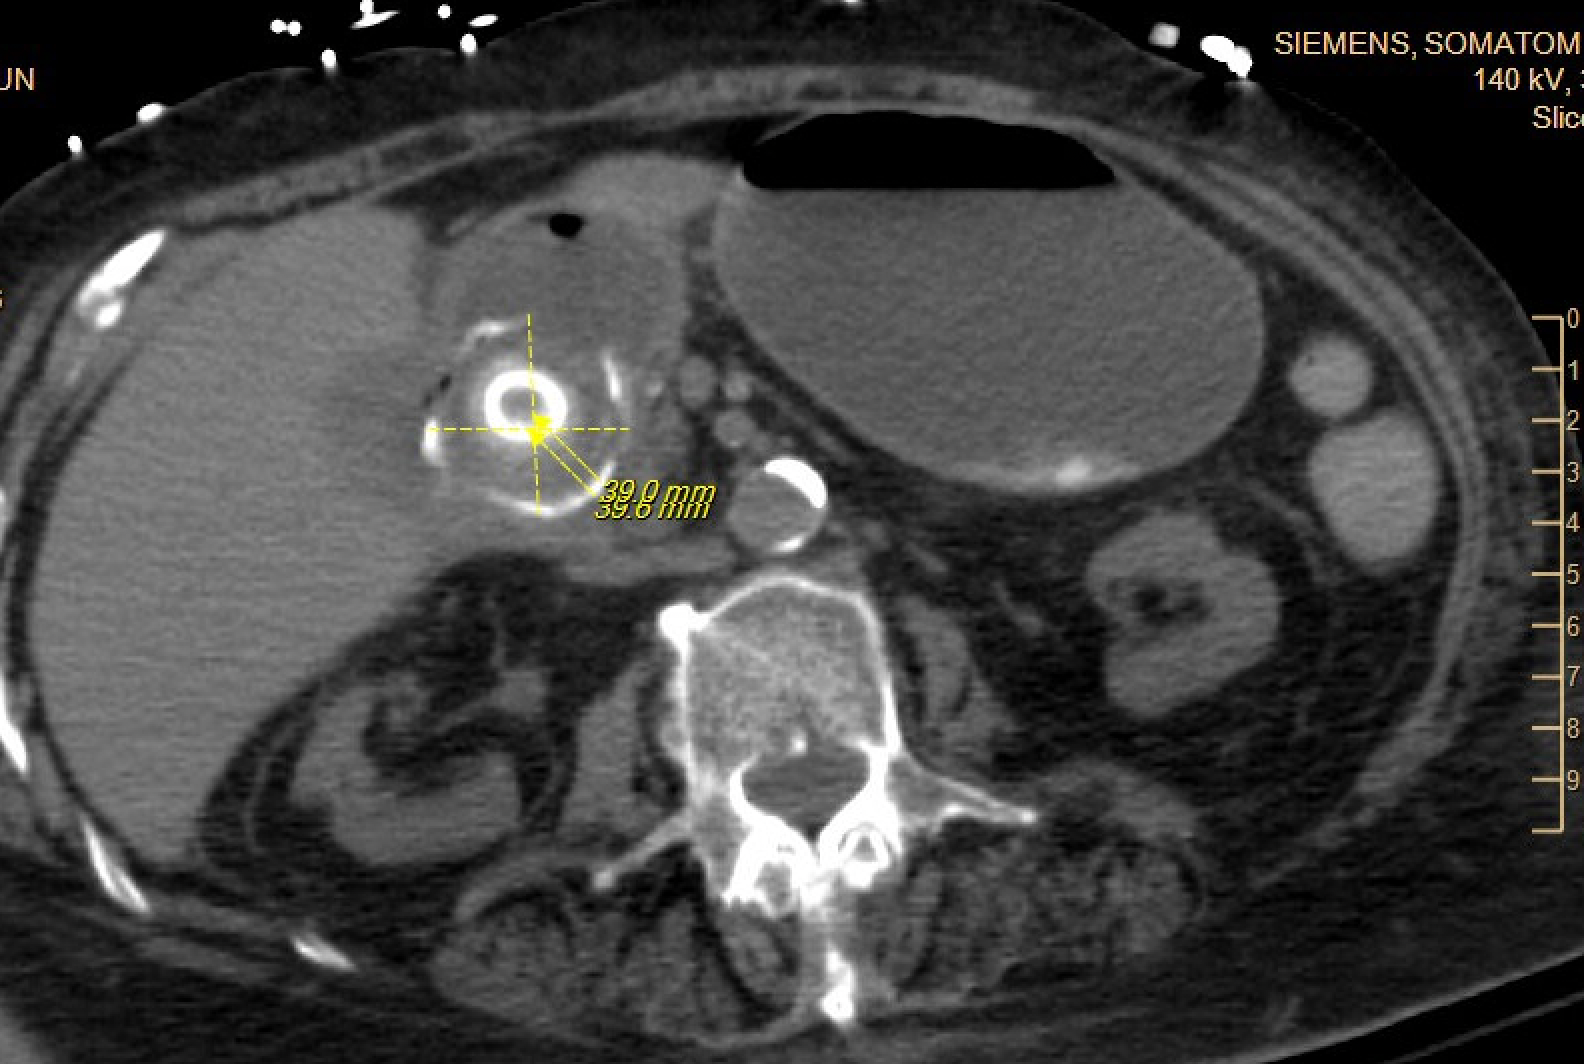

Case Presentation: An 84-year-old woman with type 2 diabetes mellitus, hypertension, prior ischemic stroke, osteoporosis, and rheumatoid arthritis presented to the hospital after a fall with altered mental status from increased home benzodiazepine use. During her admission, she developed acute nausea and vomiting with a new leukocytosis and was found to have acute cholecystitis. She underwent placement of a percutaneous cholecystostomy tube (PCT), completed intravenous antibiotics, and was discharged with the PCT in place. During her rehabilitation stay, her PCT was accidentally removed. She followed up with general surgery and was advised of the risk of gallstone complications, but given her frailty, the decision was made to allow for additional recovery prior to an elective cholecystectomy. Three months later, the patient presented to the emergency room with two days of abdominal pain, nausea, and vomiting. She had normal vital signs, and exam was notable for mild generalized abdominal tenderness, distention, and decreased bowel sounds. Laboratory evaluation revealed a white blood cell count of 21,100 cells/ul, a hemoglobin of 11.1 g/dL, normal sodium and chloride levels, a bicarbonate level of 36 mmol/L, blood urea nitrogen of 34 mg/dL, creatinine of 2.02 mg/dL (baseline is between 1.3 and 1.5 mg/dL). She had marked gaseous gastric distention on her initial abdominal x-ray. Subsequent computed tomography scan of the abdomen showed interval fistulization of the gallbladder and the gastric antrum/first portion of the duodenum with multiple gallstones extending through the fistula into the stomach and duodenum, resulting in gastric outlet obstruction, known as Bouveret syndrome. A nasogastric tube was placed for gastric decompression, and she underwent esophagogastroduodenoscopy for lithotripsy and removal of the gallstones. Attempted removal of the stones led to an esophageal tear. An esophageal stent was placed, but the patient developed bilateral empyemas requiring chest tube placement. She had a prolonged hospital course during which she was intubated and required enteral feedings through a nasojejunal tube.